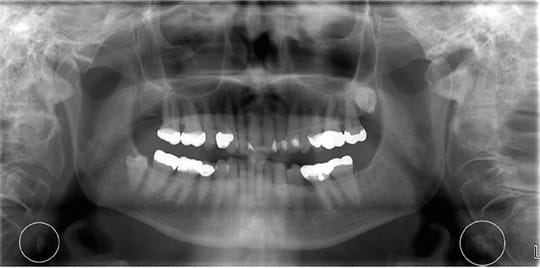

On a PAN, carotid artery calcification (CAC) can appear as a radiopaque lesion that is either rounded or nodular in shape (see Images 1 and 2).9,10 CACs most often present themselves between the C3 and C4 vertebrae. They can be localized to one side or appear bilaterally.10 Moshfeghi et al. stated, “Panoramic radiographs may help us to detect CACs in patients with or without other associated risk factors.”10 This means dental hygienists may be the first ones to discover these in their patients.

area of the carotid bifurcation in a 78-year-old female patient. Image courtesy and used with permission from Kalid Aziz, DDS, MS, and Lucinda J. Lyon, RDH, DDS, EdD.9